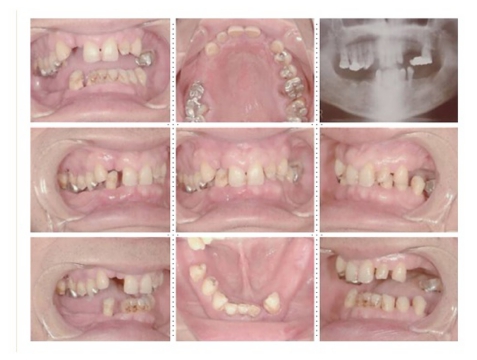

症例8

62才 男性

このようなケースは、残存歯を残すのか抜歯かの決断に迫られます。もし私の口腔内がこのケースだった場合、どの治療法を選択するのかをお話します。10年後、15年後を考慮し残存歯は全て抜歯し、上下顎共に8本ずつインプラントを埋入することにしました。

顎骨の質・量ともに十分でインプラント埋入は簡単です。ブリッジを製作する時の咬み合わせが一番問題となり、仮歯の段階で十分に咬合を安定させ、ブリッジ製作には技工士との連携が必要となります。今までこの様なインプラントのフルブリッジをセット後、インプラントが抜けた事は1度もありませ ん。